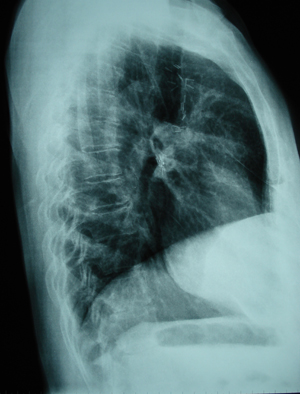

Εικόνα 2

Πλάγια ακτινογραφία θώρακος. Στρογγυλή σκίαση πάνω από το επίπεδο της πύλης στο πρόσθιο τμήμα του άνω λοβού.